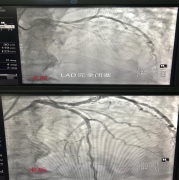

我院第一例急診PCI順利完成

一位73歲的患者,于7月26日凌晨3點因發(fā)作性胸悶3天伴加重伴憋喘3小時入院,查體示呼吸急促,端坐位急性憋喘狀態(tài),BP90...